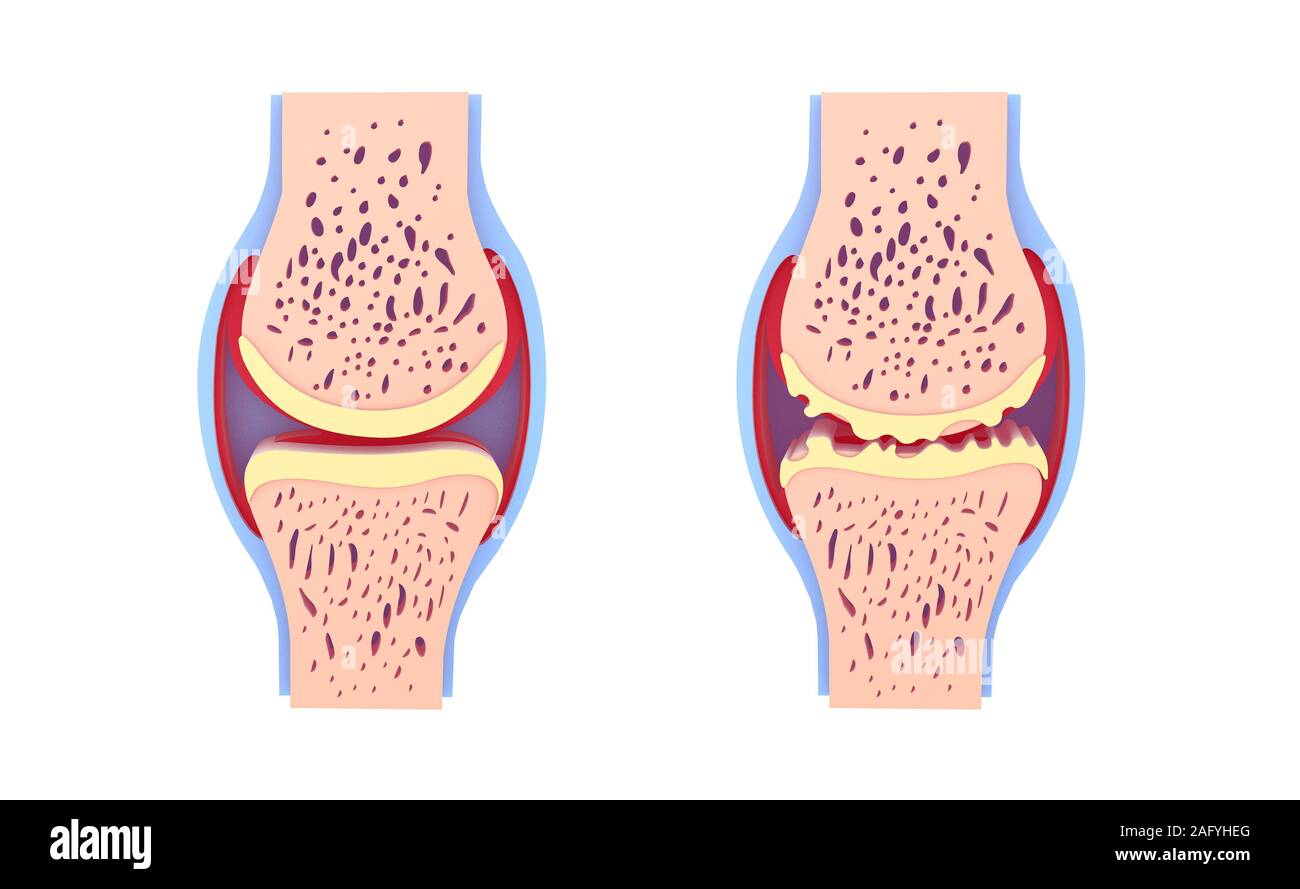

Anatomy of the joint of a healthy knee on the left, and one deformed by osteoarthritis on the right. Stock Photohttps://www.alamy.com/image-license-details/?v=1https://www.alamy.com/anatomy-of-the-joint-of-a-healthy-knee-on-the-left-and-one-deformed-by-osteoarthritis-on-the-right-image476924956.html

Anatomy of the joint of a healthy knee on the left, and one deformed by osteoarthritis on the right. Stock Photohttps://www.alamy.com/image-license-details/?v=1https://www.alamy.com/anatomy-of-the-joint-of-a-healthy-knee-on-the-left-and-one-deformed-by-osteoarthritis-on-the-right-image476924956.htmlRF2JKWPJ4–Anatomy of the joint of a healthy knee on the left, and one deformed by osteoarthritis on the right.

Anatomy of the joint of a healthy knee on the left, and one deformed by osteoarthritis on the right. Stock Photohttps://www.alamy.com/image-license-details/?v=1https://www.alamy.com/anatomy-of-the-joint-of-a-healthy-knee-on-the-left-and-one-deformed-by-osteoarthritis-on-the-right-image476925002.html

Anatomy of the joint of a healthy knee on the left, and one deformed by osteoarthritis on the right. Stock Photohttps://www.alamy.com/image-license-details/?v=1https://www.alamy.com/anatomy-of-the-joint-of-a-healthy-knee-on-the-left-and-one-deformed-by-osteoarthritis-on-the-right-image476925002.htmlRF2JKWPKP–Anatomy of the joint of a healthy knee on the left, and one deformed by osteoarthritis on the right.

3d illustration of healthy synovial joint and with osteoarthritis. Images isolated on white background front view. Vivid colors. Stock Photohttps://www.alamy.com/image-license-details/?v=1https://www.alamy.com/3d-illustration-of-healthy-synovial-joint-and-with-osteoarthritis-images-isolated-on-white-background-front-view-vivid-colors-image336823272.html

3d illustration of healthy synovial joint and with osteoarthritis. Images isolated on white background front view. Vivid colors. Stock Photohttps://www.alamy.com/image-license-details/?v=1https://www.alamy.com/3d-illustration-of-healthy-synovial-joint-and-with-osteoarthritis-images-isolated-on-white-background-front-view-vivid-colors-image336823272.htmlRF2AFYHEG–3d illustration of healthy synovial joint and with osteoarthritis. Images isolated on white background front view. Vivid colors.

3d illustration of healthy synovial joint and with osteoarthritis. Images isolated on white background leaning on the floor. Vivid colors. Stock Photohttps://www.alamy.com/image-license-details/?v=1https://www.alamy.com/3d-illustration-of-healthy-synovial-joint-and-with-osteoarthritis-images-isolated-on-white-background-leaning-on-the-floor-vivid-colors-image336823265.html

3d illustration of healthy synovial joint and with osteoarthritis. Images isolated on white background leaning on the floor. Vivid colors. Stock Photohttps://www.alamy.com/image-license-details/?v=1https://www.alamy.com/3d-illustration-of-healthy-synovial-joint-and-with-osteoarthritis-images-isolated-on-white-background-leaning-on-the-floor-vivid-colors-image336823265.htmlRF2AFYHE9–3d illustration of healthy synovial joint and with osteoarthritis. Images isolated on white background leaning on the floor. Vivid colors.